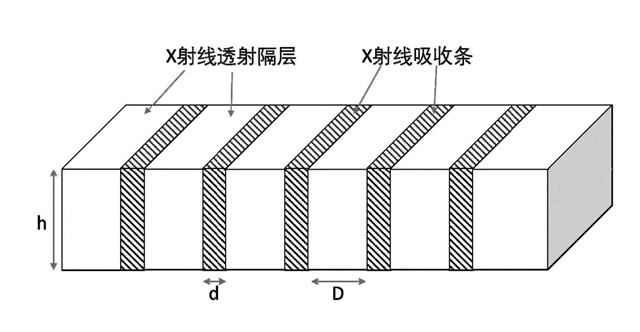

焦距(f):断面看铅条延长线会聚点到栅板垂直距离,即栅板焦距(半径)。栅密度(N):每厘米范围内含有的铅条数,一般40~65线/cm。栅比(R):铅条高度与栅条间隙之比,比值越高滤除散射线能力越强,一般8:1~14:1之间。结构组成:3~5mm薄板,用0.05~0.1mm铅条,夹持在铝或纸之间平行或按斜率排列,相邻铅条间用易透X线物质填充定位、黏合,如木、纸、铝片等。